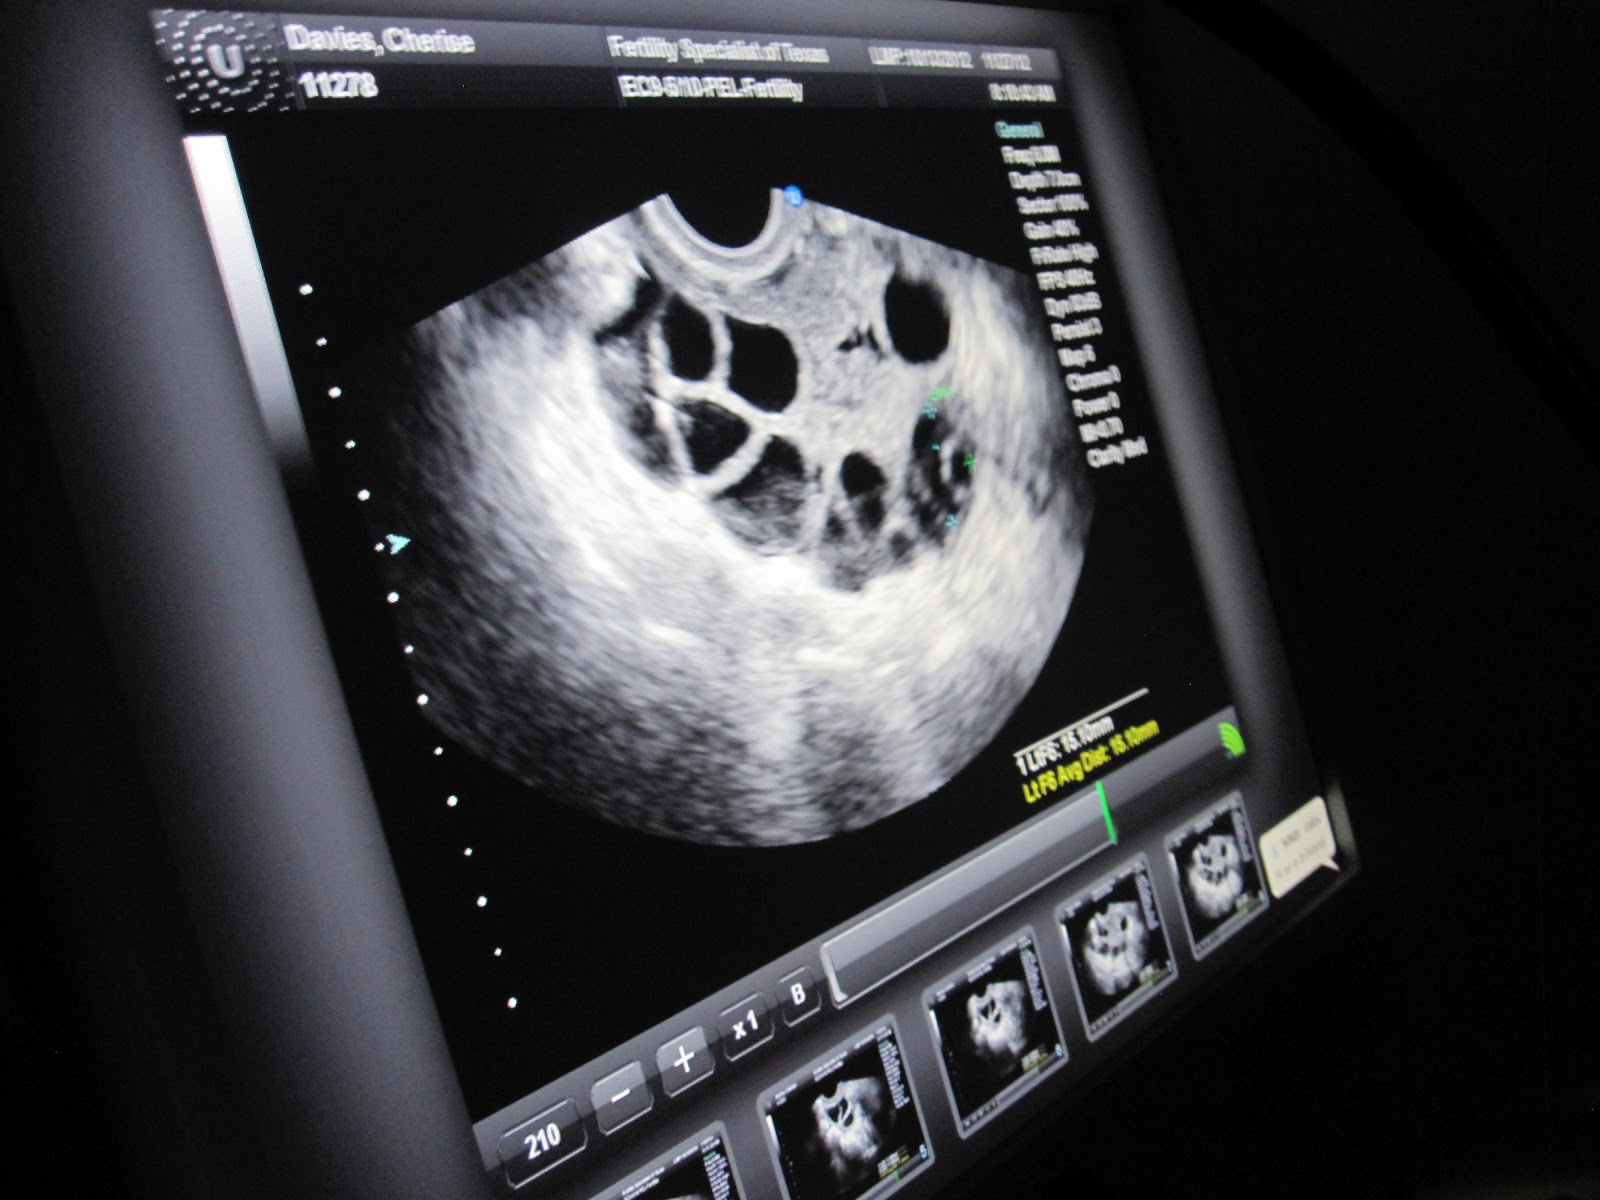

So near the end of the stimulation phase this is what my ovaries were looking like. (These pics are all from Nov. 27th. ..... the retrieval was on the 30th)

AAAND here's my LEFT ovary.

It's just one view--- Remember, the ovary is round so there are follicles on all sides.

(They ended up getting 17 follicles just from this ovary alone....and that's only the ones mature enough to take. They don't retrieve small ones.)

FYI: Normally an ovary is the size of a walnut.

By the time I got to the end of stims, they were each the size of tomatoes.

FYI-2: The nurse took these pics for me during the ultrasound so I could just watch. She was awesome.